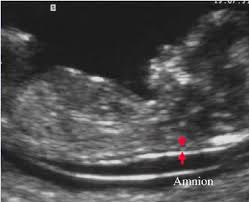

An NT scan (Nuchal Translucency scan) is a special ultrasound done during early pregnancy to measure the fluid-filled space at the back of a baby’s neck.

- What is measured? The thickness of the nuchal translucency (NT)

What is Considered Normal?

- Usually less than 3 mm is considered normal

- The exact normal range depends on the baby’s size (CRL – crown-rump length)